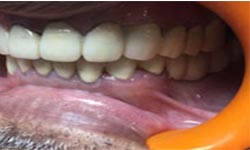

(9) Metal Ceramic Crowns

Before Treatment

After Treatment

Mr. Shiv Narayan Singh,aged 78yrs, came with a concern of multiple broken and mobile teeth with difficulty in chewing food. So, multiple RCTs followed by metal-ceramic crowns were delivered to the patient ,restoring his beautiful smile.